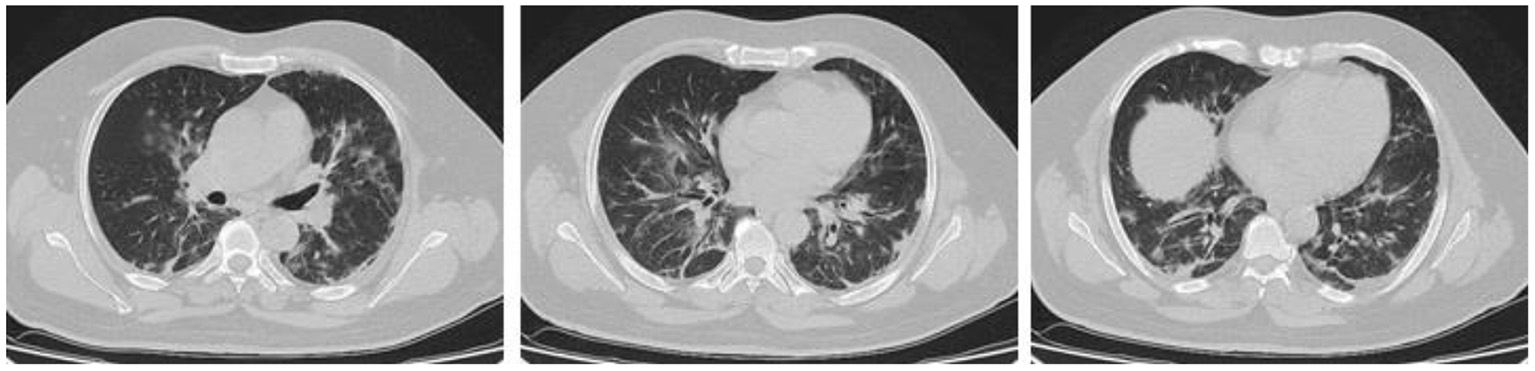

In the present study, 160 males and 70 females were enrolled to explore the association of lung CT findings in COVID-19 with patients' age, body weight, vital signs, and medical regimen. The reported major lung CT scan findings were GGO in 47 (20.4%) patients; calcified nodules in 3 (1.3%) patients; atelectasis and fibrotic band in 16 (7.0%) patients; pleural effusion and consolidation in 22 (9.6%) patients; infiltration and pneumonia in 11 (4.8%) patients; and emphysematous changes in 11 (4.8%) patients of the study sample (230 participants). Three different cases with major lung changes are shown in Figures 1–3. However, one case with minor lung CT scan findings is shown in Figure 4.

Figure 2. High resolution, axial non-enhanced spiral chest CT images (lung window) of a 59-years old patient who was confirmed to be infected by COVID-19 and admitted to hospital with Flu-like symptoms and gastrointestinal tract symptoms (mostly diarrhea). CT images show multiple faint patchy consolidations disseminated in ground-glass patterns.

Figure 3. High resolution, axial non-enhanced spiral chest CT images (lung window) of a 50-years old patient who was confirmed to be infected by COVID-19 and admitted to hospital with fever and dry cough. CT images show several airspace opacities, ground-glass shadows, and multiple sub-segmental consolidations most pronounced in the lower lobe of both lungs.